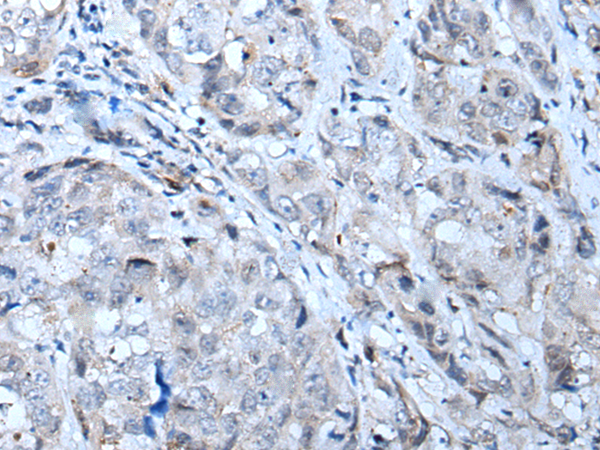

分类: 科研抗体货号: P05898别名: MKS12应用: WB,IHC反应种属: Human